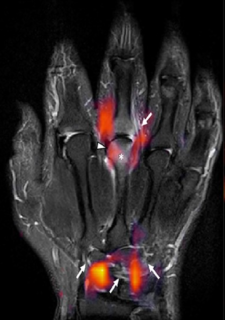

FAU-Forschungsteam wertet mit künstlicher Intelligenz MRT-Scans aus, um Art der Arthritis zu klassifizieren

Informatiker vom Lehrstuhl für Informatik 5 (Mustererkennung) der FAU und Ärzte aus der Medizinischen Klinik 3 – Rheumatologie und Immunologie sowie des Radiologischen Instituts des Uniklinikums Erlangen haben in einer Studie untersucht, ob neuronale Netze anhand von MRT-Bildern der Hände erkennen können, ob eine rheumatoide Arthritis (RA) oder eine Psoriasis-Arthritis (PsA; „Schuppenflechterheuma“) vorliegt. Das Ergebnis: Die KI konnte die beiden Arten in 75 Prozent der Fälle unterscheiden.

Für die Studie hat das Team um den Informatiker Lukas Folle fünf unterschiedliche MRT-Sequenzen von 649 Patient/-innen für das Training und das Testen eines innovativen neuronalen Netzwerkes verwendet. Das Netzwerk konnte in 75 Prozent der Fälle anhand der MRT-Aufnahmen die Patient/-innen bezüglich der Arthritisform richtig klassifizieren.